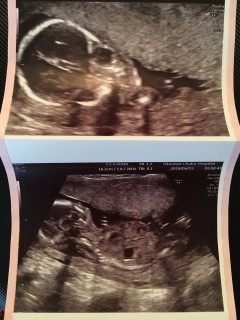

検診のたび大きくなっていて、毎月エコーが楽しみです。今回も元気に動いていました。写真は横顔です。お股を見せてくれましたが、まだ性別分かりそうにないとのことで、次回にお預け。(もしかして女の子?)大きさは約12cm。双角子宮なので安静にします…

始めての3D! 背中を向けて寝ている姿がパパにソックリ(笑) 大きさも問題なく、順調と言っていただけました。 性別は男の子かな?との事。 次は4週間後、、長いなー。楽しみです!